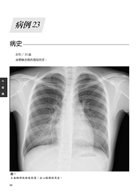

病例23 血管肉瘤(Angiosarcoma) 98